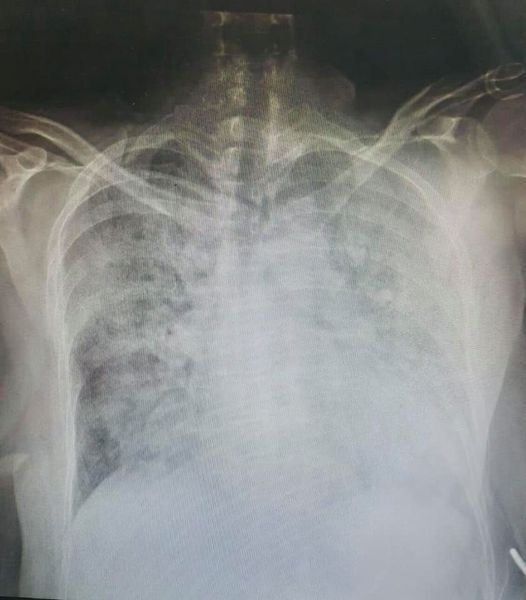

По состоянию на воскресенье, 24 октября, в Клинической больнице скорой помощи во Львове находится 415 пациентов с подтвержденным диагнозом коронавируса COVID-19, из которых 49 в тяжелом состоянии.

Никто из этих людей не получил ни одной дозы вакцины против пандемии.

"Посмотрите в глаза тем 50 пациентами, не вакцинированы, в полном сознании задыхаются, потому легкие просто уничтожены – сгорели от проклятого вируса! И медикам, которые падают с ног и уже не выдерживают, посмотрите в глаза", – призвала врач.